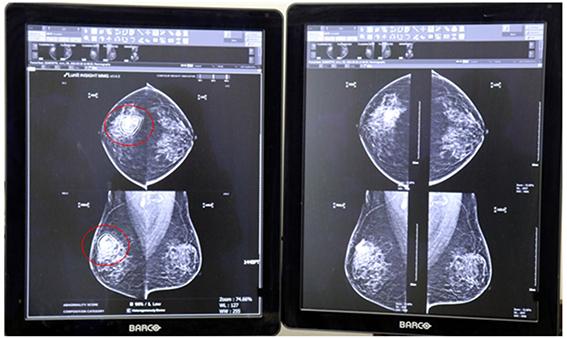

• AI 루닛 인사이트 MMG 전국 16개 건강증진의원에 도입

한국건강관리협회(이하 건협)는 유방촬영에서의 판독오류를 줄이고 정확도를 높이기 위해 지난 3월 19일 인공지능(AI)판독보조시스템 루닛 인사이트 MMG를 전국 16개 지부 건강증진의원에 도입했다.

이 판독보조시스템은 유방암 의심 부위를 검출하여 위치 정보와 의심 정도를 표기해 영상의학전문의의 진단을 보조하는 시스템이다. 특히 유방 조직의 밀도에 따라 나타날 수 있는 판독오류를 AI로 최소화해 정확한 판독과 진단에 활용하게 된다.

건협 광주전남지부 문운현 영상의학전문의는 “여성암발생 1위인 유방암은 조기에 발견하고 치료하는 것이 무엇보다 중요하다. 유선조직이 촘촘하게 모여 있는 치밀유방의 경우 유방암 병소가 조직에 가려져 판독에 어려움이 있을 수 있는데 이번 인공지능(AI)판독보조시스템 도입으로 유방암을 조기발견하는 데 도움이 될 것이라 기대한다”고 말했다.